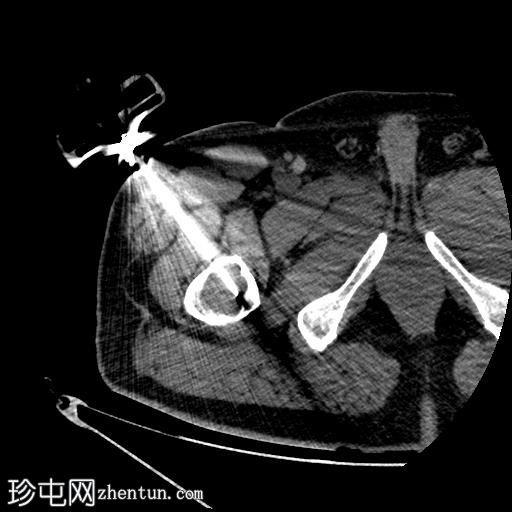

轴位

平扫

行CT引导下病变穿刺活检,术中及术后均未见并发症。

将活检针置于右股骨近端干骺端溶骨性透亮肿块中心后,从囊性病变中抽取血液。穿刺活检结果为阴性,未见骨髓浸润。因此,囊性病变的血液样本被送检进行组织病理学检查,结果显示无恶性肿瘤